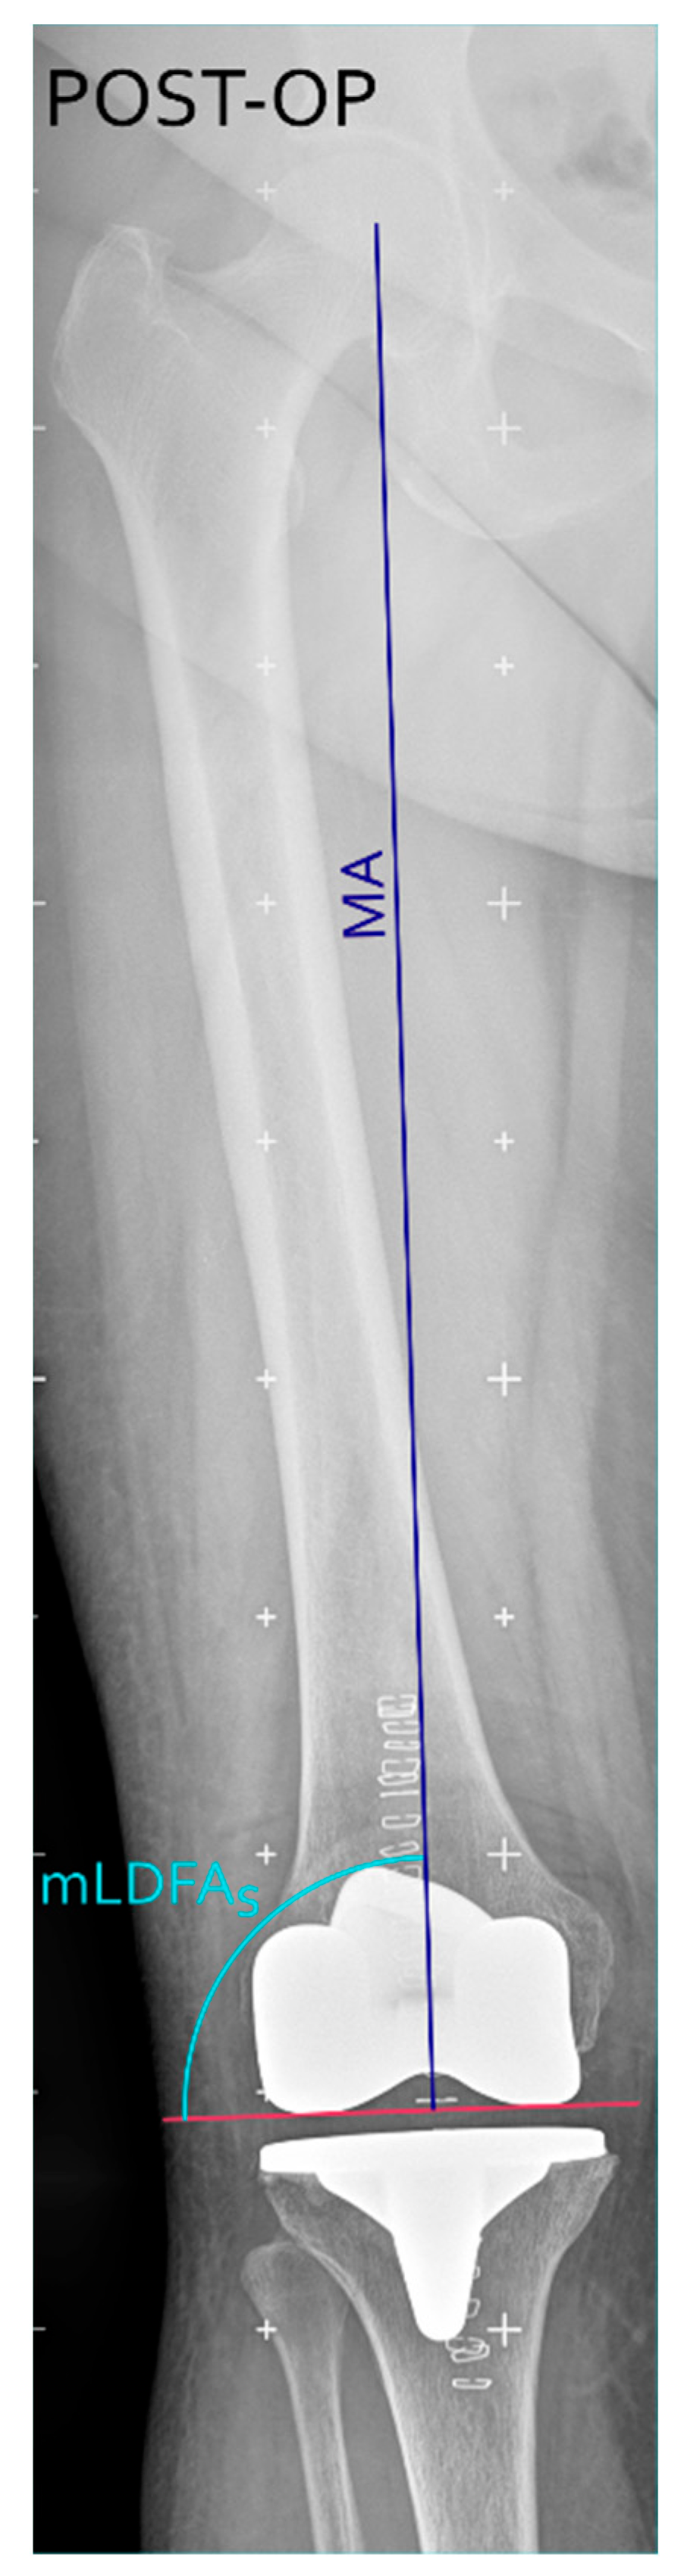

To quantitatively assess the accuracy and reproducibility of the proposed technique for distal femoral resection, we considered original mechanical lateral distal femoral angles (mLDFAo), mLDFAp, surgical mechanical lateral distal femoral angle (mLDFAs, i.e., the post-operative mLDFA measured on long leg X-rays) (see Figure 4) and the resection error (defined as the difference between mLDFAp and mLDFAs) as follows.

Figure 4. Postoperative long-leg coronal X-ray, showing the postoperative component positioning with the surgical mechanical lateral distal femoral angle (mLDFAs, in light blue) defined as the angle between the distal femoral cut (purple horizontal line) and the MA (blue line). Figure created with Inkscape (version 1.4.3, The Inkscape Project, Boston, MA, USA).